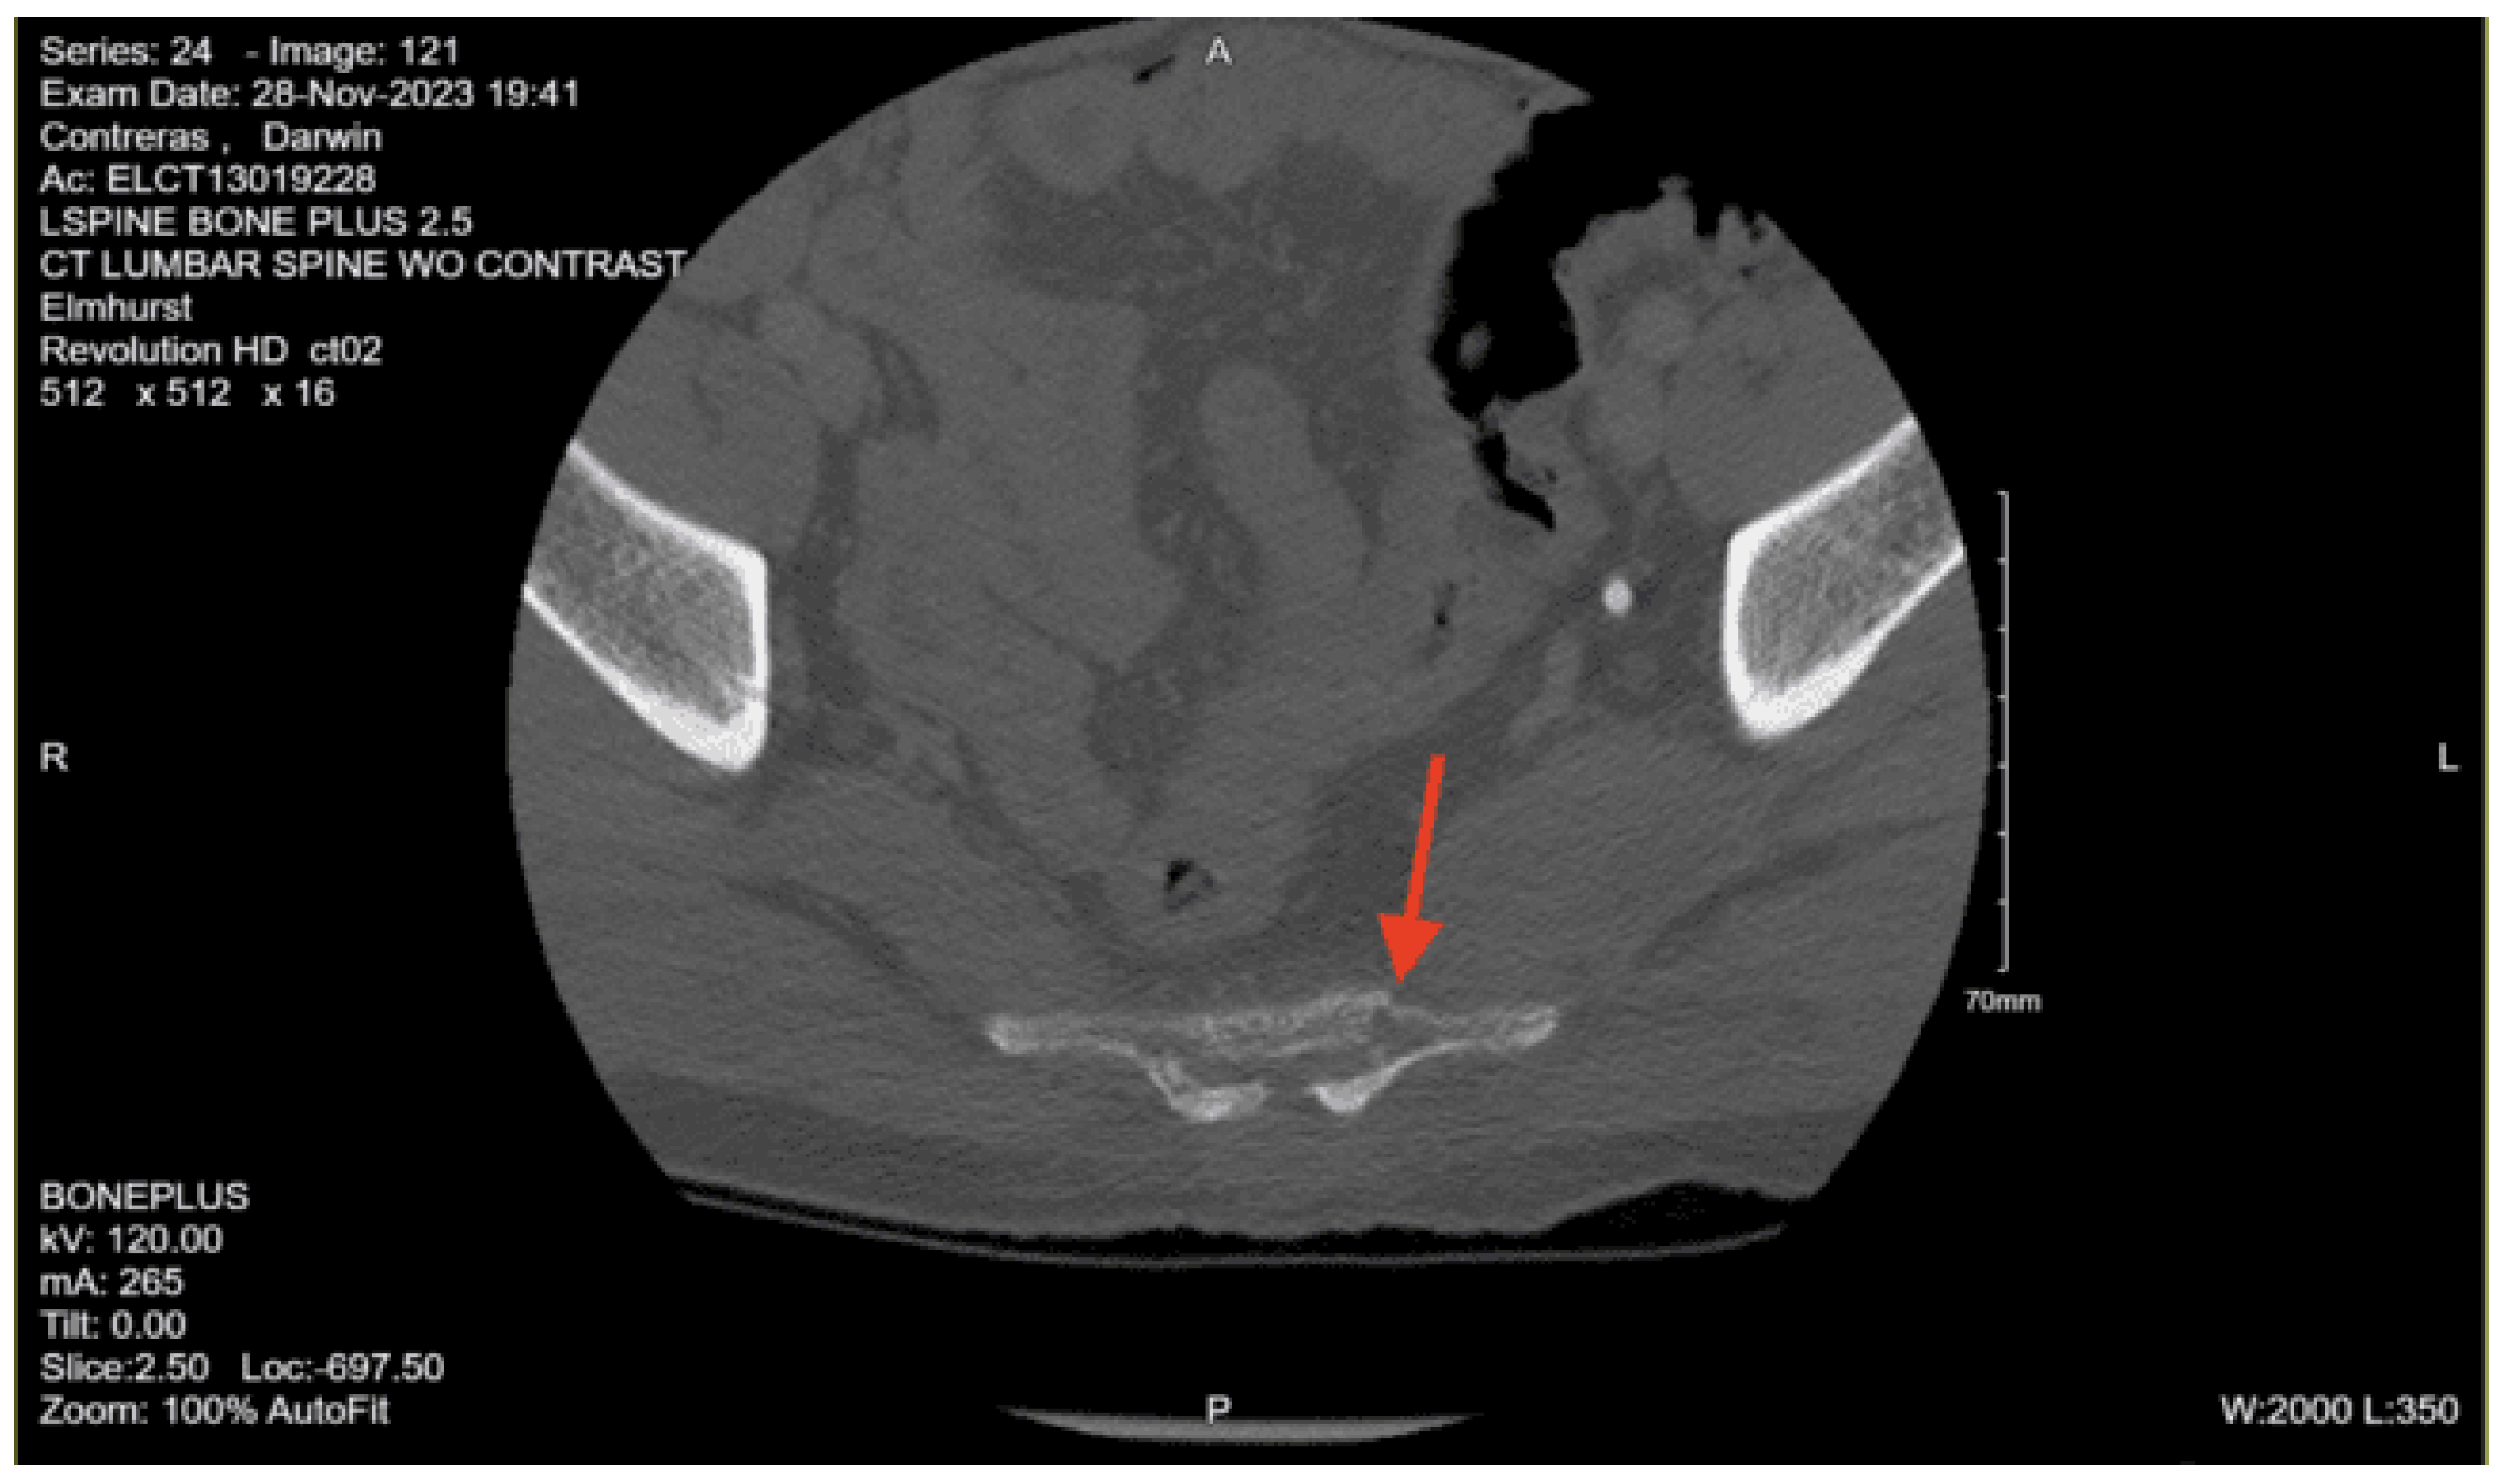

CT lumbar spine w/o contrast: Nondisplaced sacral fracture, approximately at the level of S4. Deformity at the sacrococcygeal junction, indeterminate chronicity. No other fractures identified. Diffuse osteopenia. Degenerative changes within the lower lumbar spine with grade 1 anterolisthesis of L4 over L5. No acute lumbar spine fractures identified

CT pelvis w/o contrast: Nondisplaced sacral fracture, approximately at the level of S4. Deformity at the sacrococcygeal junction, indeterminate chronicity. No other fractures identified. Diffuse osteopenia. Degenerative changes within the lower lumbar spine with grade 1 anterolisthesis of L4 over L5